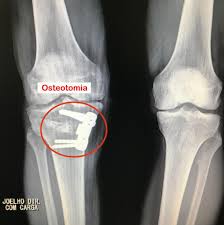

O Sistema Convencional De Placa E Parafusos Na Osteotomia Tibial Alta Em Cunha De Abertura Medial E Suficientemente Estavel Um Estudo Retrospectivo Sciencedirect

Revista Brasileira De Ortopedia O Sistema Convencional De Placa E Parafusos Na Osteotomia Tibial Alta Em Cunha De Abertura Medial E Suficientemente Estavel Um Estudo Retrospectivo